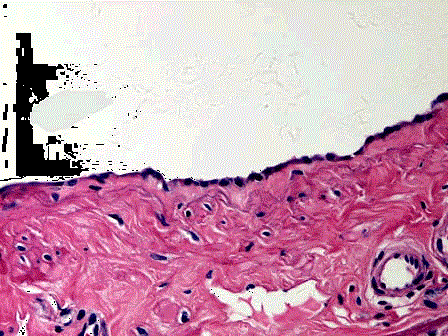

问题 女性,28岁,剖腹产时发现左侧卵巢包块5cm×3cm×2cm,表面光滑(如图),切开内含清亮、淡黄色液体,显微镜下见囊内壁衬单层立方上皮细胞(如图),应诊断为 ( )

选项 A.浆液性囊腺瘤 B.浆液性交界性囊腺瘤 C.浆液性囊腺癌 D.黏液性囊腺瘤 E.黏液性交界性囊腺瘤

答案 A